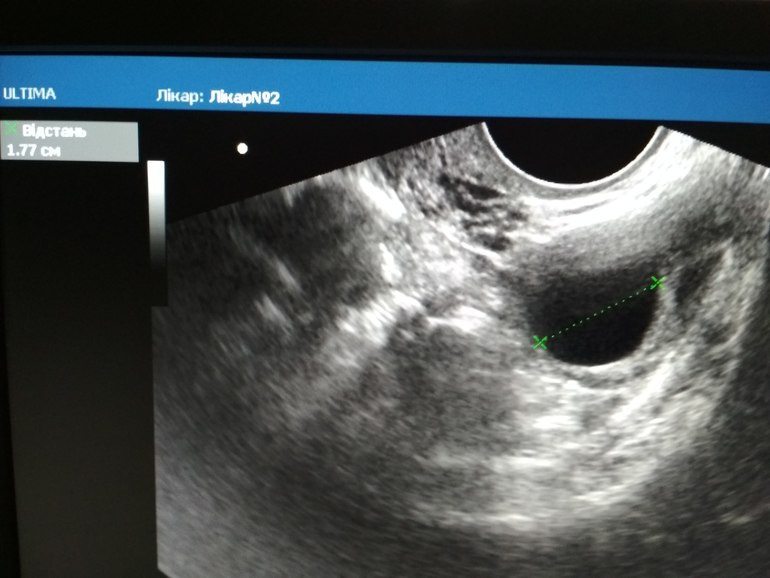

Месячный циклДобрый день.Может кто сможет объяснить ,почему фолликула не имеет четкий контур?УЗИ на 10 дц. Утром тест на овуляцию нулевой.

Добрый день.Может кто сможет объяснить ,почему фолликула не имеет четкий контур?УЗИ на 10 дц. Утром тест на овуляцию нулевой.